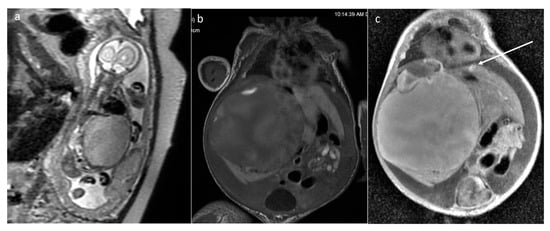

| Teratoma | sacrococcygeal | 25 | 268 [2.5–1145.165] | yes (13/17) [918–1661) | cystic (6) mixed (19) | yes 8/13 | yes (3/4) |

| head and neck | 13 | 176.1 [1.78–877.11] | yes (9/13) (796–1294) | solid (3) mixed (8) cystic (2) | yes (8/13) | yes (1) | |

| thorax and abdomen | 8 | 32 [1.49–134.98] | yes (3/6) | mixed (3) solid (3) cystic (2) | yes (4/5) | yes (1) | |